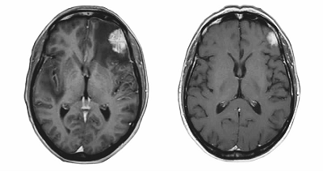

HER2阳性乳腺癌可以扩散到大脑(左图十字所示);一些患者已经被证明,接受靶向治疗对减少转移是有效的(右)